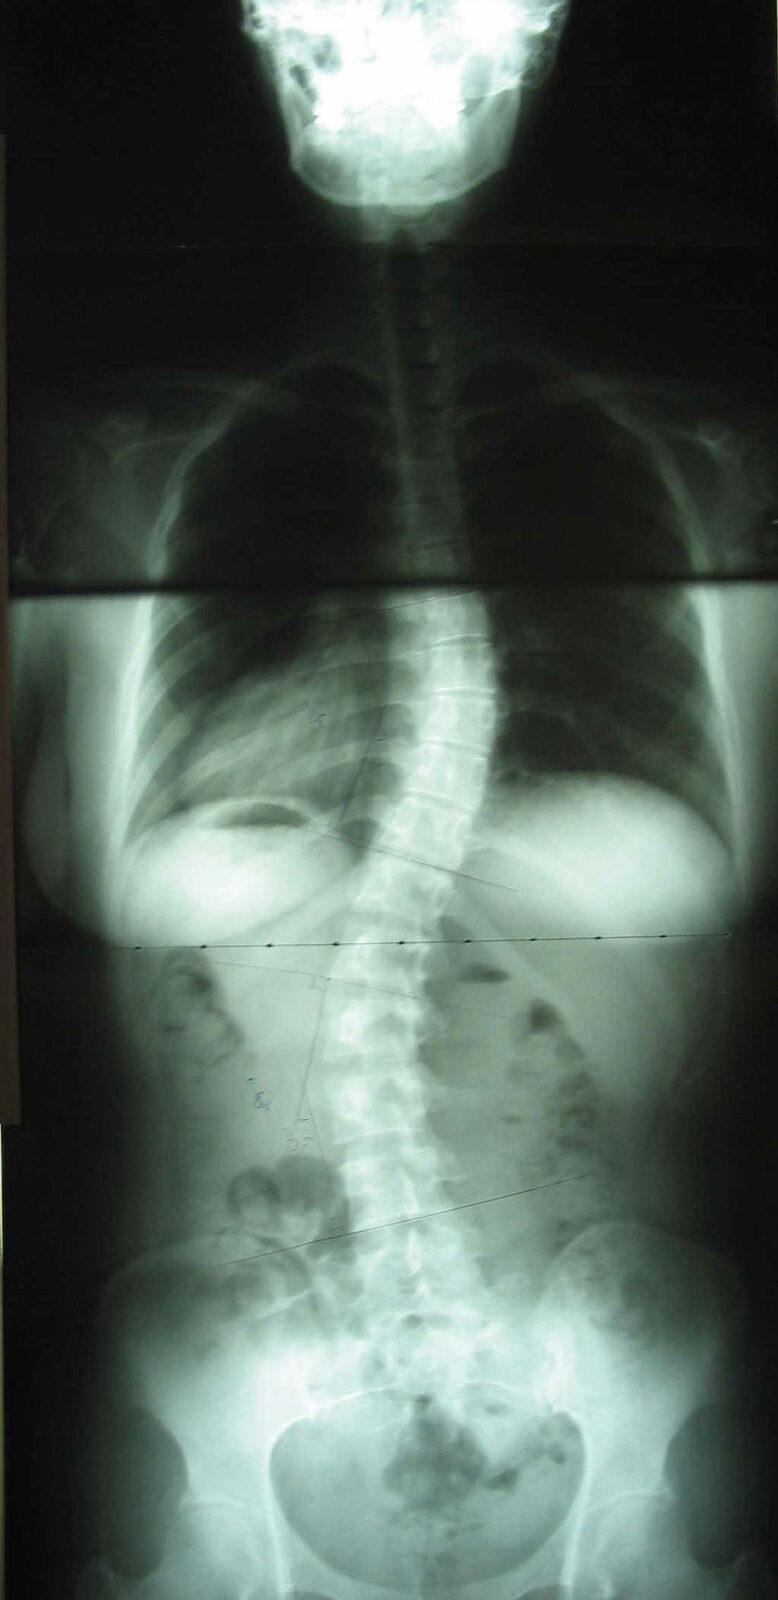

척추 측만증의 분류

선천적인 척추의 골기형이나 후천적인 발육저하로 발생되는 측만이 아니라 특별한 이유 없이 어느 순간부터 발생되는 측만증을 특발성 측만증 또는 척추 구조적 측만증이라 부릅니다